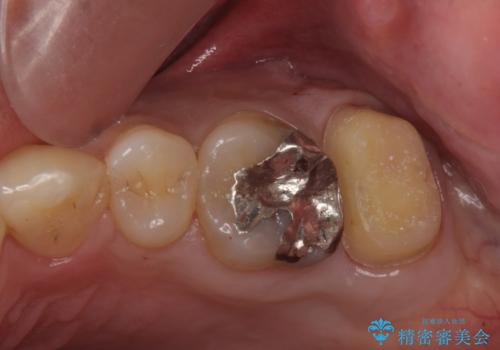

- 奥歯のザラザラが気になり、白い被せ物をしたいとのことで来院。

レントゲンや拡大鏡で確認をしたところ歯の表面は粗造になっていたが

う蝕があるわけではないので以下の提案を行った。

①ジルコニアクラウンによる治療

表面のザラザラは消えるが健全な歯質を多く削ることになる。

以上の提案より患者様に考えてもらい、①をご希望されたのでジルコニアクラウンによる治療を行った。